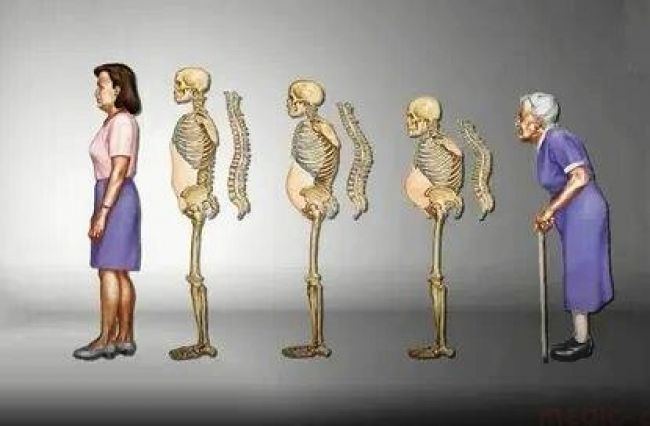

Правильная осанка для пожилых людей

Раздел: Кадры мудрости